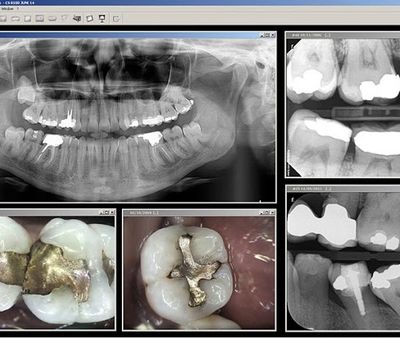

Radiographs (x-rays) are an essential part of quality endodontic therapy. Our offices utilize an advanced non-film dental imaging system known as CDR (computed dental radiography). The already low radiation required for dental radiographs is further reduced by over 80% compared to conventional film. Using this system, an electronic sensor produces computerized radiographs which appear instantly on a chairside computer screen. These images can then be optimized, printed, archived indefinitely and sent to your dentist.

Our office employs the use of CCD/CID/CMOS sensors to produce direct digital images. Direct digital radiography has many advantages over silver halide film, such as speed, reduced radiation, environmental waste reduction, elimination of darkroom costs, and lossless e-mail image transfer and documentation.